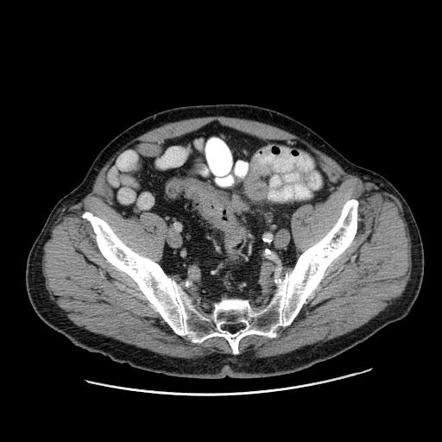

Рак прямой кт